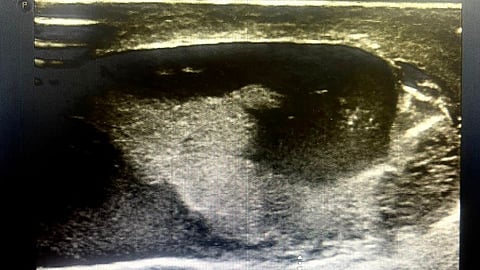

وصل لقسم الطوارئ بمجمع الملك فيصل بالطائف شاب يعاني تهشمًا شديدًا بالخصية اليسرى، مع تجمع دموي حولها نتيجة حادث مروري.

وأوضحت "صحة الطائف" في تصريح إلى "سبق" أنه على الفور تم إجراء عملية استكشاف جراحي للخصية اليسرى، أثبت وجود تهشُّم في غلاف الخصية، وفقدان أكثر من 50 في المئة من الغلاف الخارجي، وتجمُّع دموي حول الخصية؛ فقرر الأطباء بقيادة الدكتور حازم السفياني، استشاري جراحة المسالك البولية، إجراء عملية عاجلة لترميم الخصية، باستخدام رقعة من أنسجة الحبل المنوي، وذلك بعد أخذ القياسات اللازمة للترقيع، والتأكد من صحة وسلامة الرقعة. وقد استغرقت العملية ثلاث ساعات.